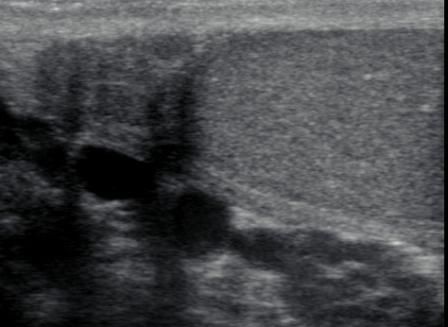

正常附睾头矢状位图像